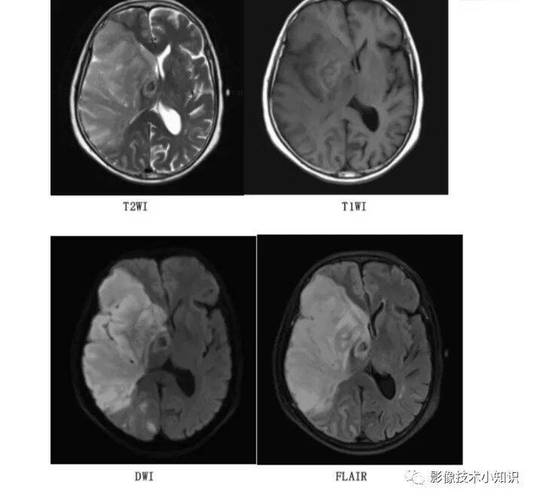

- 关键序列:弥散加权成像

- 这是发现早期脑梗死的“王牌”序列!

- 原理: DWI主要探测的是水分子的布朗运动,在急性脑梗死早期,细胞毒性水肿导致细胞内水分子增多,且这些水分子被限制在缩小的细胞空间内,运动受到限制(即“水分子扩散受限”)。

- 表现: 在DWI图像上,这种“水分子扩散受限”的区域会显示为明显的高信号(亮白色),这个改变在脑缺血发生后的几分钟内就可能开始出现,并且在发病后30分钟到1小时内,诊断的敏感性和特异性就非常高了。

- 其他重要序列:

- 表观弥散系数: 与DWI配对使用,可以帮助确认DWI上的高信号是真的梗死,还是其他伪影,真正的梗死在ADC图上会显示为低信号(暗黑色)。

- 液体衰减反转恢复: 对水肿非常敏感,在早期也能看到梗死区域呈高信号,但不如DWI特异,因为它也会受其他病变(如炎症、肿瘤)影响。